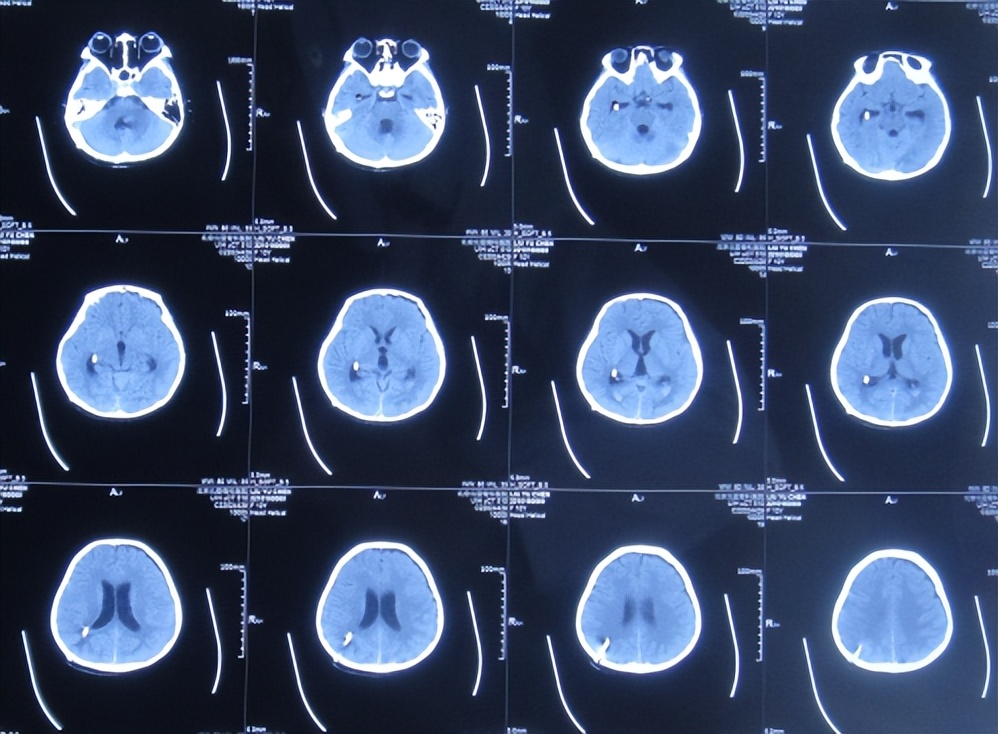

2023年1月9日(住院治疗85天即脑胶质瘤切除术后81天)出院,出院时:意识清楚,头痛恶心完全消失,自己走路不稳( 图-19 );出院时肺部感染变好、颅脑CT示无异常( 图-20 )。

图-19: 2023年1月9日出院时

图-20: 出院时颅脑CT